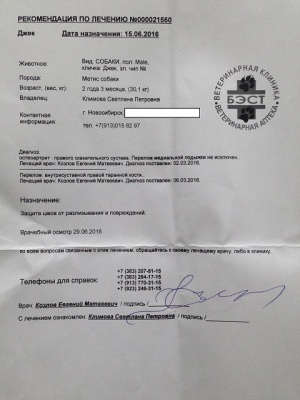

Лист приема и назначений от 15.06.2016, итоговый чек за период 02.03.2016 - 07.06.2016.

Последний раз были на приеме у Козлова Е.М. 01.07.2016.

Евгений Матвеевич не только произвел осмотр, но и внимательно посмотрел на Джека в движении, на улице, при ходьбе по лестнице. Следующий плановый осмотр через два месяца. Два месяца реабилитации и обучения жизни на четырех лапах.

О Джеке. За прошедший период по результатам контрольного осмотра 03.09.2016 Джек признан лечащим врачом Козловым Е.М. (оперирующий хирург, клиника Бэст) абсолютно здоровым и выписан без каких либо ограничений. Важен контроль состояния, в период весна/осень возможны боли, что проявится хромотой, и необходимо будет применение Превикокса.